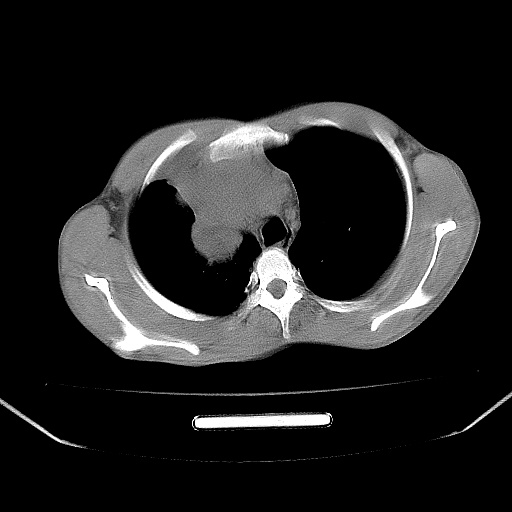

以下是引用zjzjr在2008-7-20 12:57:00的发言:[br]考虑为生殖源性肿瘤(内胚窦瘤),侵袭性胸腺瘤可能性大;右侧少量胸腔积液。

以下是引用xinliheng001在2008-7-20 21:17:00的发言:[br]右纵隔巨大分叶状软组织均质密度肿块,右上肺叶受压明显,纵隔右移、胸膜受累有少量积液和结节样增厚。应增强扫描一定会有更具诊断价值的信息。

以下是引用xinliheng001在2008-7-20 21:17:00的发言:[br]右纵隔巨大分叶状软组织均质密度肿块,右上肺叶受压明显,纵隔右移、胸膜受累有少量积液和结节样增厚。应增强扫描一定会有更具诊断价值的信息。